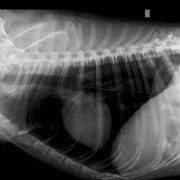

Нас 6-ро, и все они замечательные ребята с большим сердцем. Эта ситуация личная для меня, и я всеми силами хочу сделать добро, вылечить животное, которое я собственноручно вытягивала с проезжей части, которого гладила, пока ему ставили капельницу и измеряли давление врачи круглосуточной ветклиники. Спокойный умный пёс, который оказался на улице по вине человека. Он не щенок, он в самом расцвете, думаю, но такой добрый, отзывчивый и спокойный, и борющийся за жизнь. У собакена перелом таза, сильные ссадины, осколки таза навредили внутренним органам и нужна операция, последующее дорогостоящее и долгое восстановление. Также есть вопросы по дерматологии, пёсель уличный - завтра врачи возьмут соскоб, чтобы попытаться восстановить волосяной покров животного.

Собаке сделали операцию, но не на тазу (таз вправили ректально), а на передней лапе, которая оказалась сломана, но в виду того, что собака была лежачей и болезненно реагировала на перемещения по клинике, про перелом выяснилось позже. Поставили спицы.

У него есть чувствительность задних лап, поэтому проводимость есть. В туалет пошел сам. Врачи говорят операция на тазу не нужна.

Цитата Саша (  )  говорят операция на тазу не нужна.У него перелом таза, что гораздо серьезнее его сломанной и прооперированной лапы. У него же таз перекошен и лучше вряд ли при постоянном движении будет. Снимки таза и пса самого осматривал опытный травматолог?

Ну дело, конечно, хозяйское, или кураторское точнее, но я бы поинтересовалась, какой прогноз лечащий врач даёт при консервативном лечении (вернее нелечении) сломанного таза и когда планируется контроль сращения. Потому что при постоянной подвижности костей в месте перелома таза есть угроза того, что пёс станет инвалидом. При правильном лечении и фиксации - выздоровеет полностью. Здесь ведь на форуме небезразличные люди собрались и советы дают из своего волонтерского опыта (вам советовали везти пса к проверенным опытом травматологам, пч все ветеринары - специалисты широкого профиля, и лишь единицы являются узкими и грамотными специалистами в определённой области, в травматологии в частности, чему учатся годами). Вашему подопечному все желают только скорейшего выздоровления, поэтому и пишут здесь

меня зовут Алена и я одна из очевидцев и посетителей Собакена. спасибо большое, за ваше внимание к нашей истории и за желание помочь!!на данный момент его снимки смотрели в САСе, а также лечащий врач моего кота (Мурыченков Евгений - отличный врач, много раз возвращал моего Зефира с того света). оба врача сейчас подтвердили что таз оперировать нет необходимости, как нам объяснили процесс заживления будет в обоих случаях аналогичный (шуруп Собакен может вырвать случайно, при постановке шурупа этого возможно повредить нервы). чувствительность ног у него в порядке. соскоб на клеща делали, но его не нашли, возможно это нарушение функции надпочечников. но нам порекомендовали полечиться от клеща после того как у него восстановится печень (сейчас множественные ушибы внутренних органов)